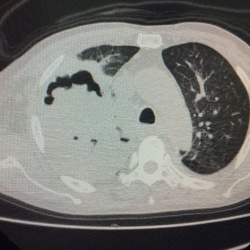

Возраст 8 лет . Был контакт с туб больным. Смущает кольцевидная тень в прикорневой зоне правого лёгкого и чуть ниже плотные округлые тени (лимфоузлы?). В боковой тоже корень не нравится. Что скажете...